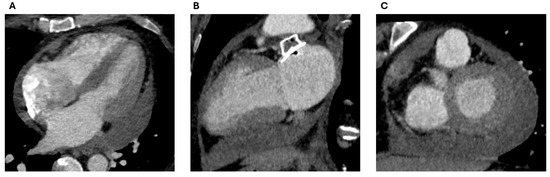

3.5. Epicardial Devices